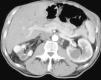

Objetivo. El oncocitoma es un tumor renal benigno, relativamente infrecuente. Hasta este momento su diferenciación radiológica del carcinoma de células renales se considera imposible, aunque hay escasos artículos en que se haya utilizado la tomografía computarizada (TC) trifásica. Los autores describen los hallazgos con TC trifásica en estos tumores, valorando si algunas características, aunque no diagnósticas, sí pudieran sugerir la posibilidad de este diagnóstico. Esto, en algunos casos, podría cambiar el manejo de los pacientes. Material y métodos. Se describen los hallazgos de TC trifásica en 10 casos de oncocitoma, vistos en 8 pacientes (un caso era multifocal-bilateral). En todos los casos el diagnóstico fue anatomopatológico, en la pieza de resección. Resultados. Todos los tumores fueron hallazgos ecográficos incidentales previos a la TC, presentando un tamaño muy variable, de 3 a 15 cm, con una media de 5,2 cm. El contorno era bien definido. Uno de los pacientes tenía tumores bilaterales (2 derechos y 1 izquierdo). Excepto en un tumor, el resto mostraban una cicatriz «estrellada» interna, que en un caso seguía un marcado patrón lobular. La captación tumoral de contraste fue ávida, con una media de 120 HU en fase arterial y 116 HU en fase excretora. La evolución de todos los pacientes fue buena, no detectándose recidivas postquirúrgicas. Conclusiones. Aunque la diferenciación con el carcinoma de células renales no puede hacerse con certeza, debe sugerirse la posibilidad de oncocitoma, fundamentalmente en tumores pequeños, con cicatriz central, ausencia de necrosis, falta de infiltración y un patrón de captación como el que se describe. Independientemente del tamaño, una morfología lobular del tumor también debe sugerir esta posibilidad.

Objective. Oncocytoma is a relatively uncommon benign kidney tumor. To date, it has been impossible to differentiate this tumor from renal cell carcinoma radiologically, although few articles report on the use of tri-phase CT in this tumor. We describe the triphasic CT findings in these tumors and evaluate whether some characteristics, although not sufficient to ensure the diagnosis, can suggest the possibility of oncocytoma. In some cases, this may lead to a different approach to the management of patients. Material and methods. We describe the tri-phase CT findings in 10 cases of oncocytoma in eight patients (one case was bilateral and multifocal). The diagnosis was made after histological examination of surgical specimens in all cases. Results. All the tumors were found incidentally at ultrasound examination prior to CT study. Tumors all had well-defined borders, and their size ranged from 3 to 15 cm, with a mean diameter of 5.2 cm. One patient had bilateral tumors (2 right and 1 left). All but one of the tumors had a star-shaped scar inside, with a marked lobular pattern in one case. All tumors showed avid uptake, with mean enhancement of 120 HU in the arterial phase and 116 HU in the venous phase. All patients evolved favorably with no post-surgical relapse. Conclusions. Although oncocytoma cannot be differentiated from renal cell carcinoma with certainty, the possibility of oncocytoma should be suggested in the case of small tumors with a central scar, without necrosis or infiltration, and an enhancement pattern as described here. Regardless of the size of the tumor, lobular morphology should also suggest this possibility.